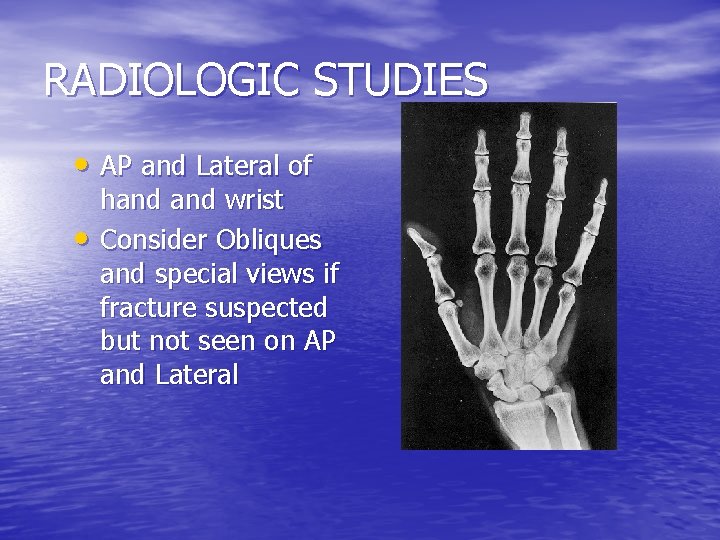

RADIOLOGIC STUDIES • AP and Lateral of • hand wrist Consider Obliques and special views if fracture suspected but not seen on AP and Lateral